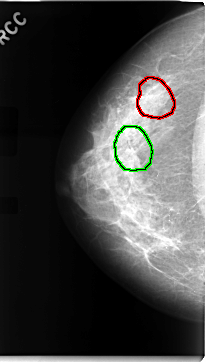

C_0068_1.RIGHT_CC

RIGHT_CC LINES 4704 PIXELS_PER_LINE 2672 BITS_PER_PIXEL 12 RESOLUTION 50 OVERLAY

FILE: C_0068_1.RIGHT_CC.OVERLAY

TOTAL_ABNORMALITIES 2

ABNORMALITY 1

LESION_TYPE CALCIFICATION TYPE AMORPHOUS DISTRIBUTION CLUSTERED

ASSESSMENT 5

SUBTLETY 4

PATHOLOGY MALIGNANT

TOTAL_OUTLINES 1

BOUNDARY

ABNORMALITY 2

LESION_TYPE MASS SHAPE ARCHITECTURAL_DISTORTION MARGINS SPICULATED

ASSESSMENT 4

SUBTLETY 2